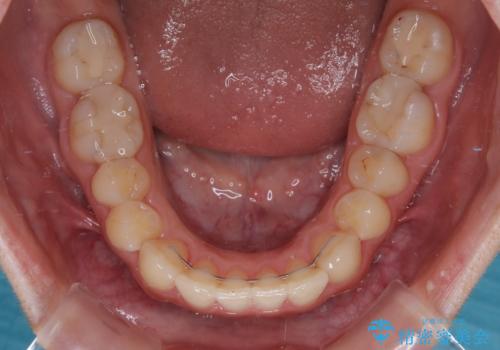

- 前歯の開咬を気にして来院された患者様です。

開咬の治療は、前歯を閉じるように動かすとともに、上下臼歯を圧下(骨内にめり込ませる)させることで進めて行きます。

インビザラインは臼歯の圧下を効果的に行えるため、インビザラインを用いて矯正治療を行うこととしました。